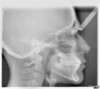

Téléradio Profil